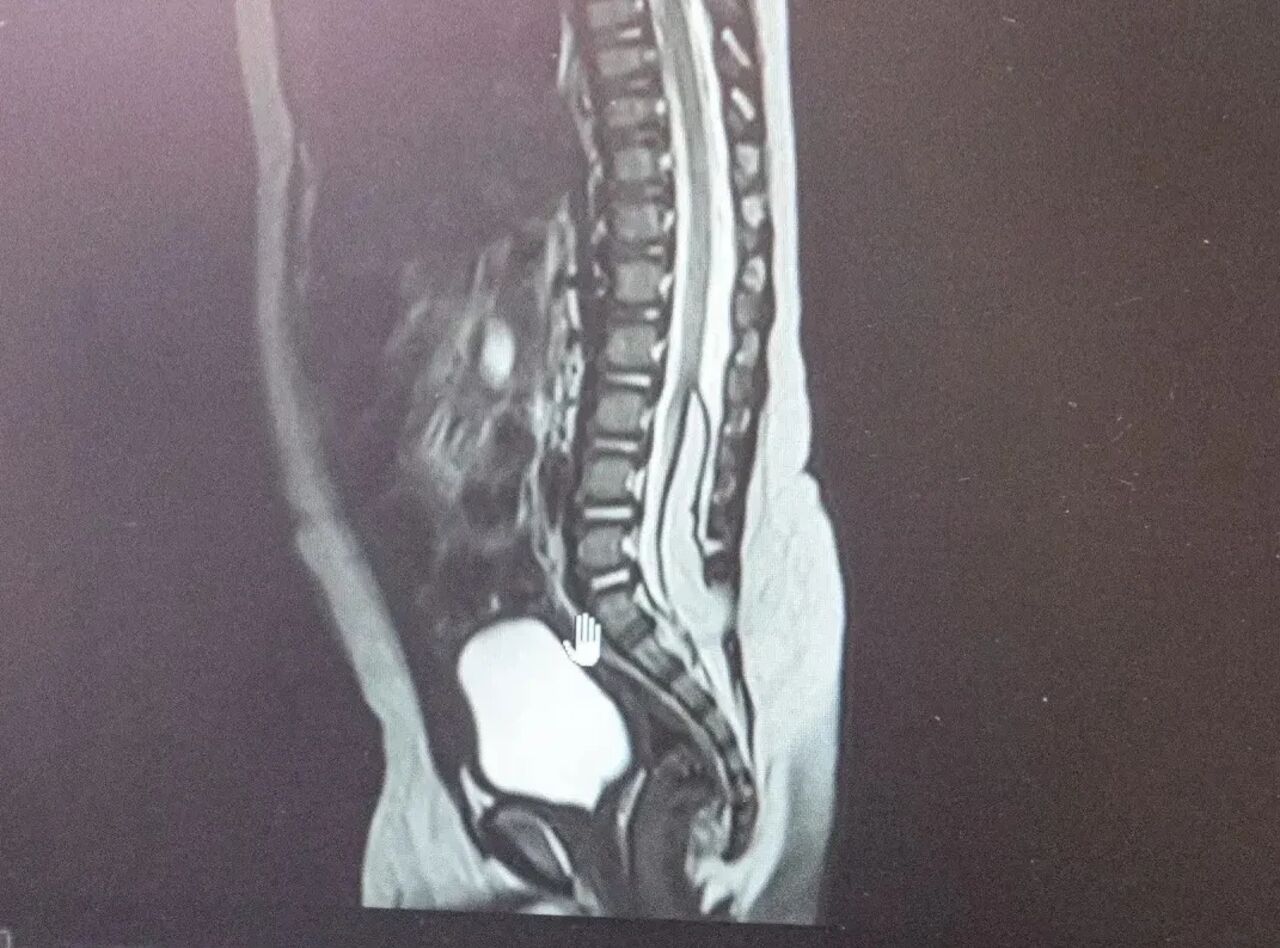

В Кузбасской областной детской клинической больнице имени Ю.А. Атаманова с начала года спасли двух малышей с пороками развития центральной нервной системы. Речь идет о пациентах в возрасте 6 и 8 месяцев, у которых врачи выявили липомиелоцеле.

Как рассказали в министерстве здравоохранения Кузбасса, это редкая аномалия, при которой патологическая жировая ткань формируется в спинном мозге, фиксируя его. В результате спинной мозг не может нормально расти и развиваться вместе с ребенком. Это может обернуться тяжелыми последствиями: нарушением работы тазовых органов и недержанию.

Фото: Министерство здравоохранения Кузбасса